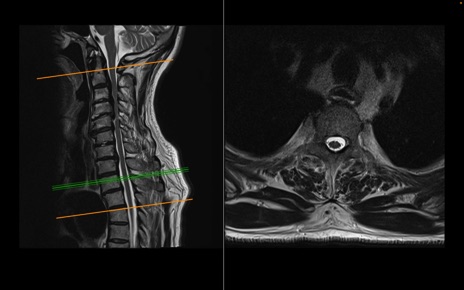

頚椎MRI

T2WI(横断像)

T2WI(矢状断像)